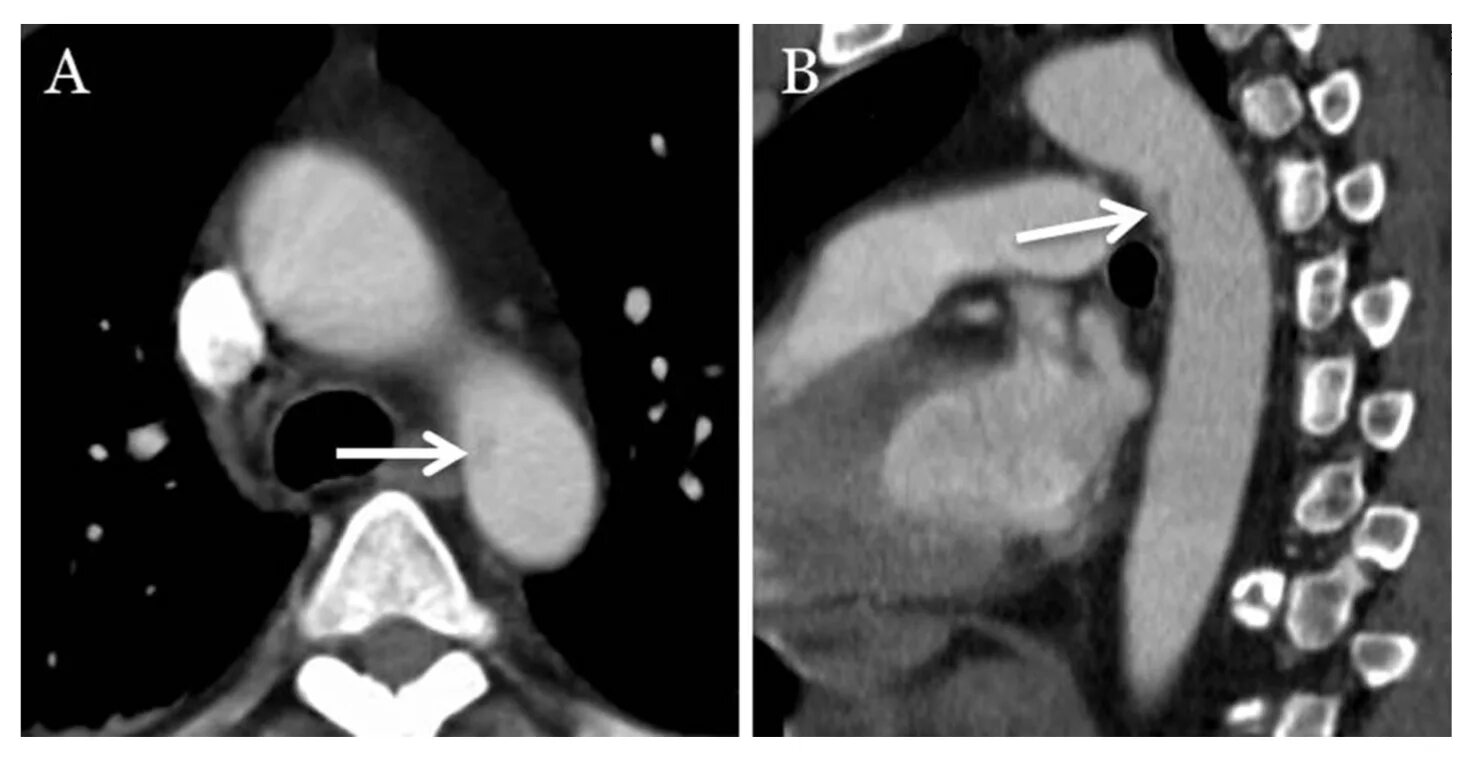

От чего бывает разрыв аорты